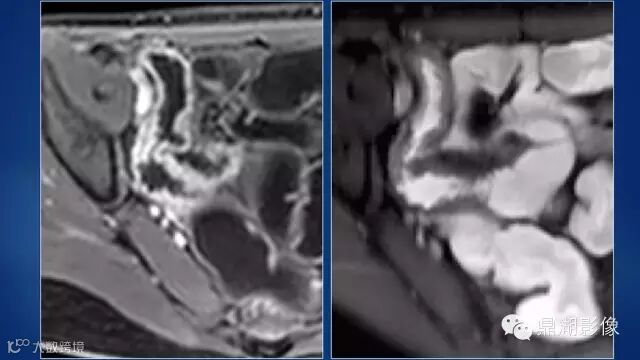

do you know comb sign?

The comb sign refers to the hypervascular appearance of the mesentery in active Crohn disease.